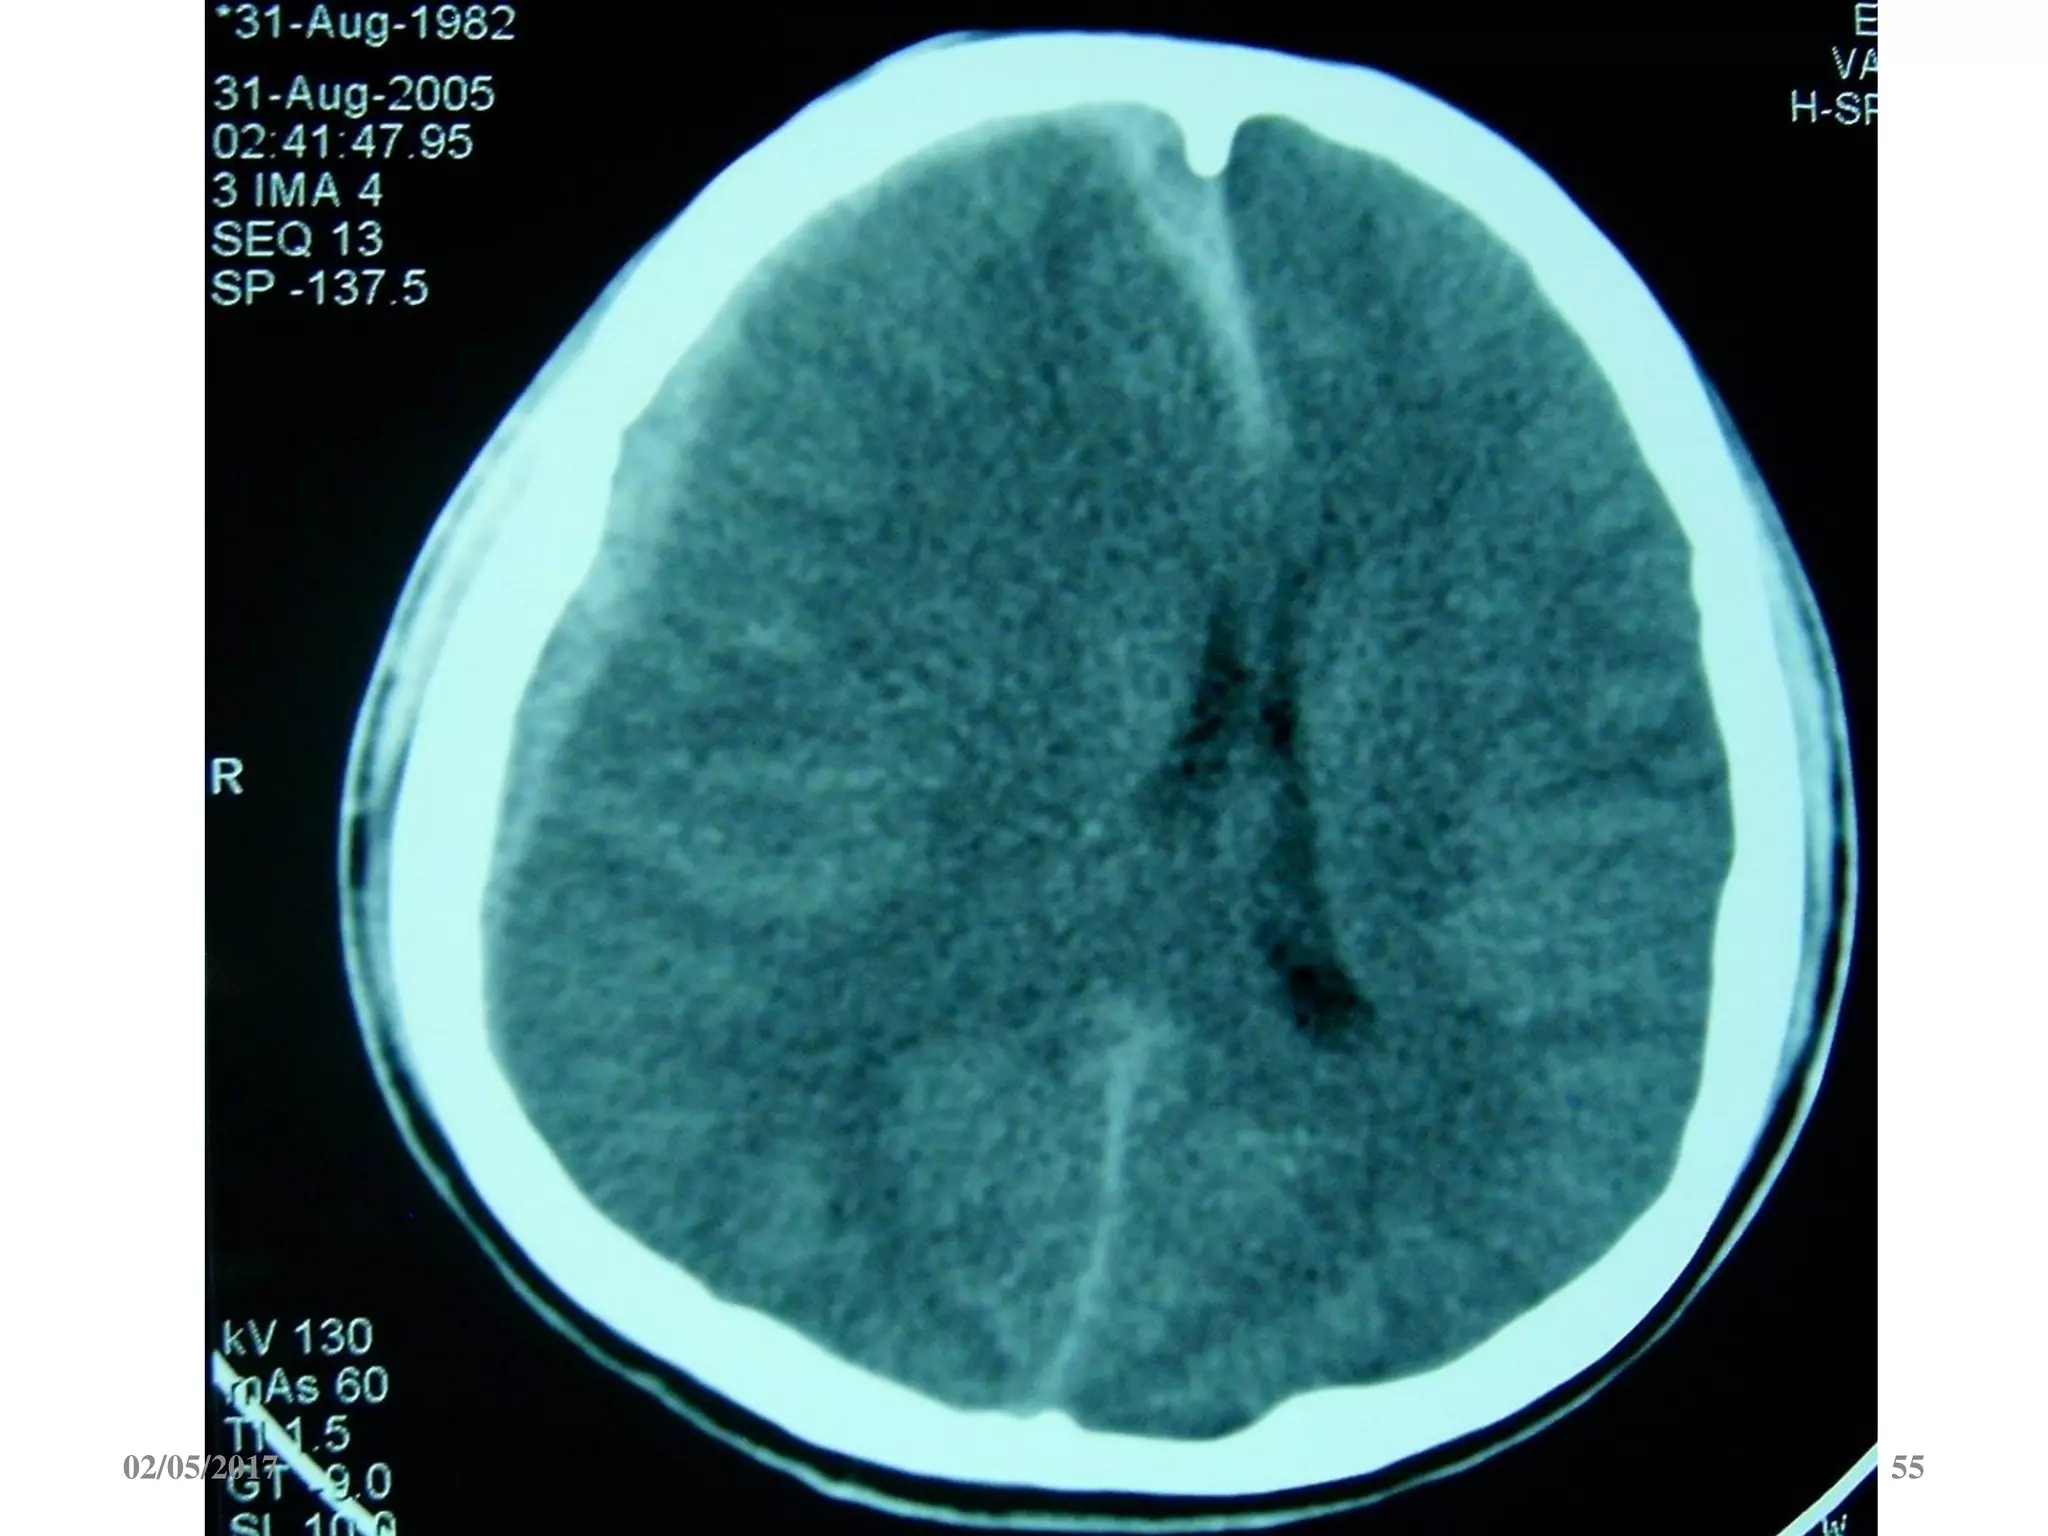

Máu tụ dưới màng cứng cấp

 Ngoài trục, hình liềm,

tăng đậm độ

 Vượt qua được các

khớp sọ

 Thường kèm dập não

02/05/2017 54

02/05/2017 55